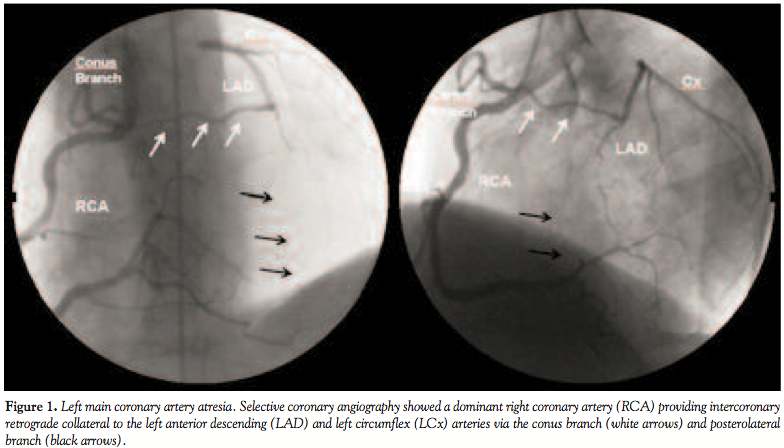

Case Report. A 65-year-old man with atypical chest pains and easy fatigue was referred for coronary angiography after positive exercise stress 201-thallium myocardial scintigraphy with a small reversible defect in the anterior and posterolateral wall. The cardiovascular examination was essentially unremarkable. The chest roentgenogram and the electrocardiogram were within normal limits. The echocardiogram showed a structurally normal heart with normal left ventricular function (ejection fraction, 65%) and no regional wall motion abnormality. On selective coronary angiography, cannulation of the left coronary ostium and direct visualization of the left coronary artery (LCA) was not possible. There was a large dominant right coronary artery (RCA) providing significant intercoronary retrograde collateral to the left anterior descending artery (LAD) and the left circumflex artery (LCx) via sinus node artery branch and posterior lateral (PL) branch (Figure 1). The main pulmonary artery was not opacified through RCA injections. The coronary arteries were free of atherosclerotic stenosis and calcifications. Left ventriculography showed normal left ventricular wall motion. There was also complete absence of left main coronary artery (LMCA) from the left aortic sinus or from any other

site in the aorta as shown by aortic root angiogram (Figure 2). In agreement with the clinical cardiologist and cardiac surgeon, the patient was managed medically with anti-ischemic, antiplatelet, and statin therapy. Surgical coronary artery revascularization was not recommended because the patient was mildly symptomatic, the extent of the ischemia on the thallium scan was not substantial, and the branches of the LCA were too narrow for revascularization. He received regular outpatient follow-up with only very mild symptoms 3 years after diagnosis.